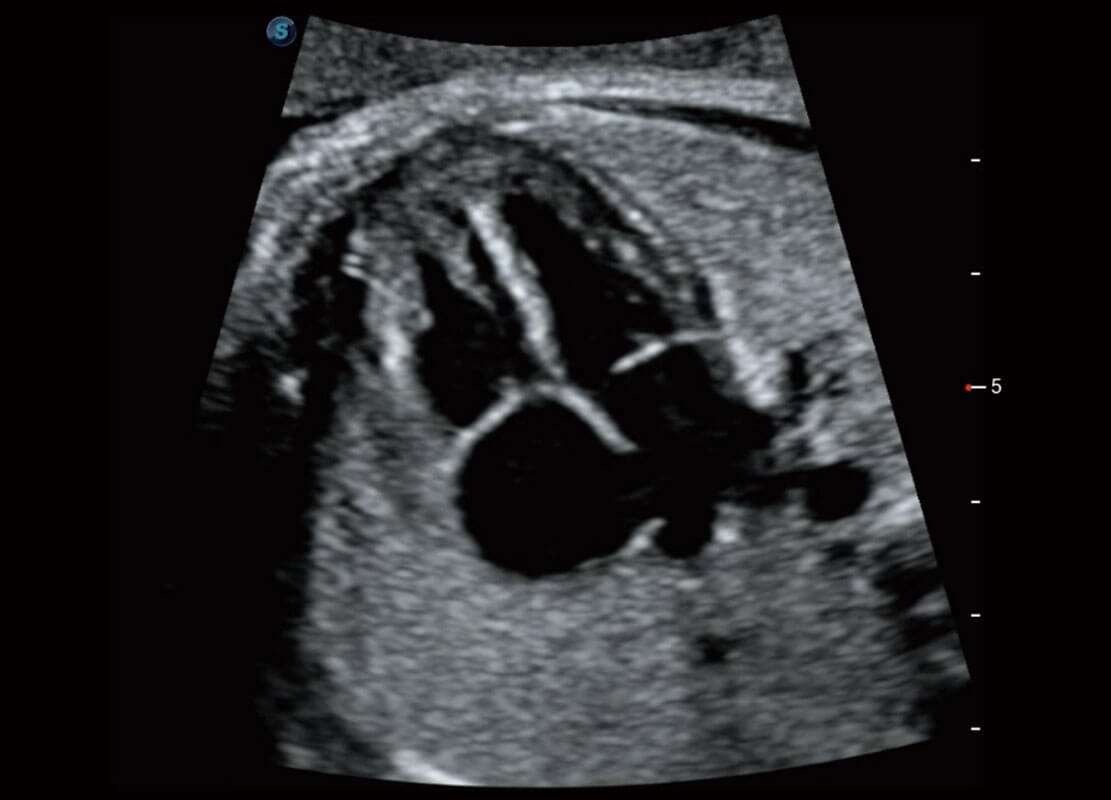

P60在胎兒早孕期超聲篩查中為您帶來優(yōu)異的圖像質(zhì)量。

早孕-胎心